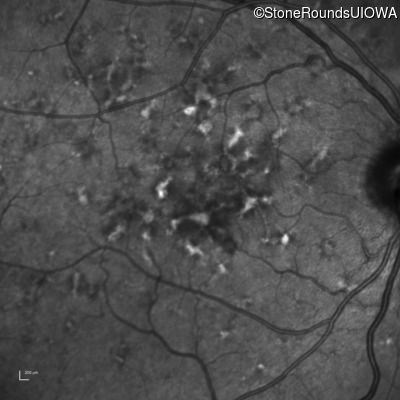

Age at visit: 49 years

Age at visit: 49 years (Visit 2)